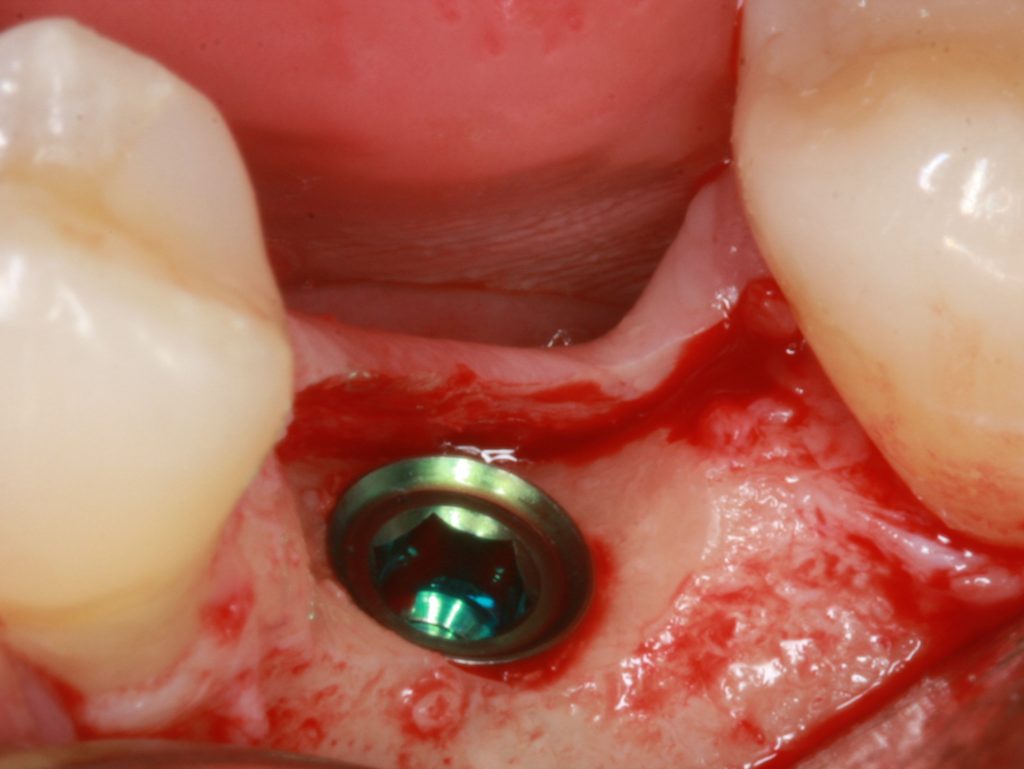

The first thought, which enters the mind, just places implant deeper subcrestally (Fig 5). Firstly, there must be enough place for the alveolar nerve that the implant could be positioned subcrestally in a safe manner.

It is advised that the implant would stop at least 1 mm over the nerve. Subcrestal placement is suggested to cause controlled bone remodeling, but not a bone loss. It is interesting to note, that not all implants can be placed subcrestally. In addition, implant-abutment connection stability becomes very important, if located subcrestally.